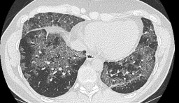

- Chest imaging such as chest X-ray or high-resolution CT scan